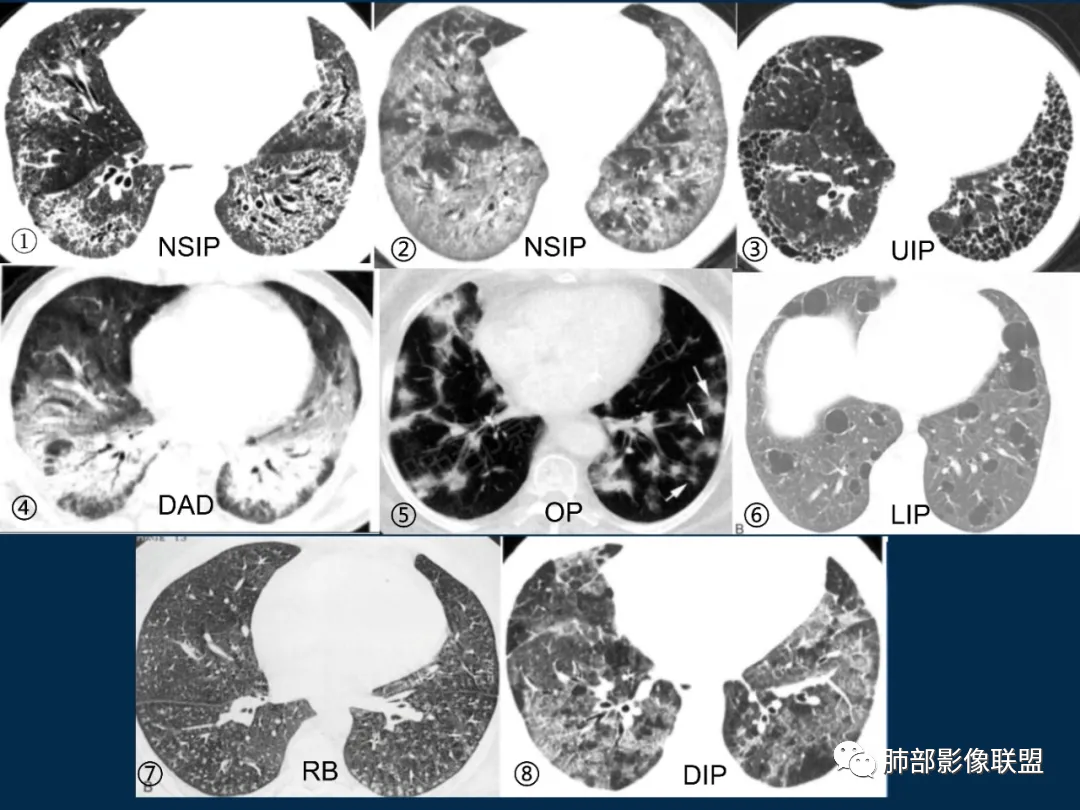

结缔组织相关性间质肺部疾病(ILD)的最常见病理类型包括非特异性间质性肺炎(NSIP),寻常间质性肺炎(UIP),机化性肺炎(OP),淋巴细胞性间质性肺炎(LIP),急性间质性肺炎(AIP)。

各种病例类型的CT表现

ILD各种病理类型